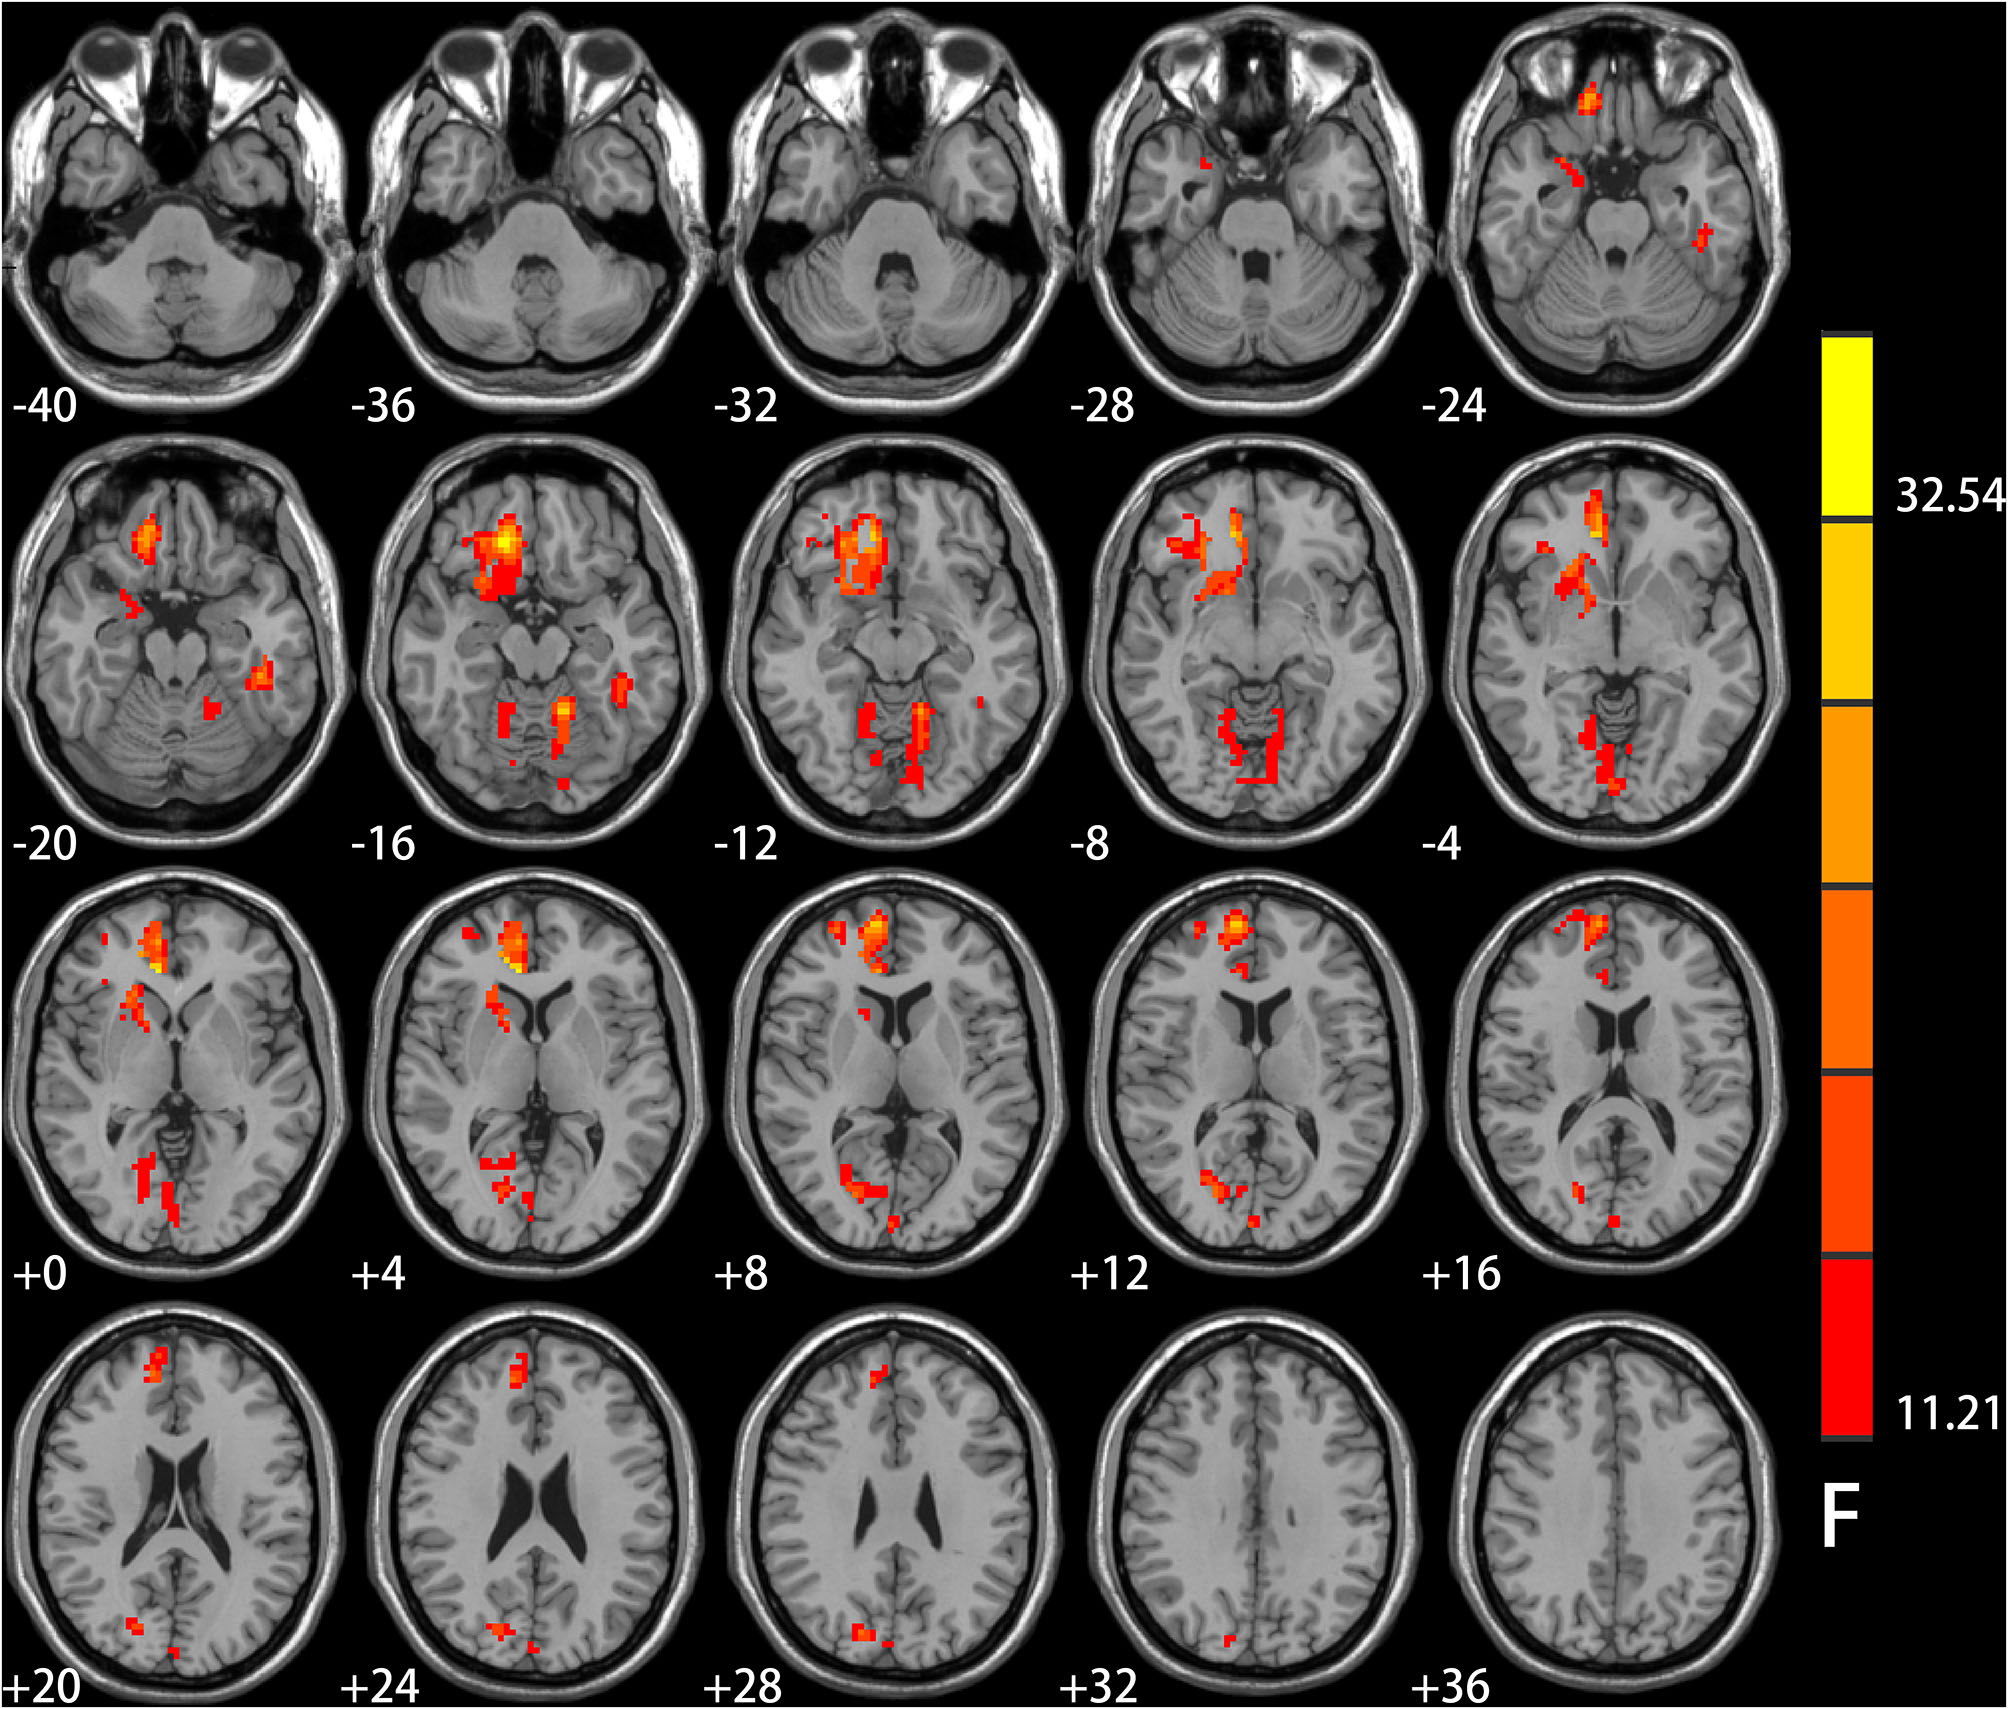

Significant IGD and smoking interaction effects on ALFF were identified in the right medial pre-frontal cortex (MPFC) (i.e., orbital frontal gyrus and anterior cingulate cortex) extending to the ventral striatum, bilateral cerebellar and visual-related regions (i.e., lingual and calcarine gyrus and cuneus) as well as the left temporal gyrus (Figure 1 and Table 2).

Figure 1

Results of ANCOVA analysis controlling for age, gender, educational level, and head motion. Brain regions showed group differences among the four groups of healthy controls, smokers, internet gaming disorder (IGD), and IGD-Smoking individuals in amplitude of low-frequency fluctuation (ALFF) (p < 0.05, FWE-corrected). The brain regions mainly involved in the right medial pre-frontal cortex (MPFC, i.e., orbital frontal gyrus and anterior cingulate cortex) extending to ventral striatum, bilateral cerebellar, and visual-related regions (i.e., lingual and calcarine gyrus and cuneus) as well as the left temporal gyrus.